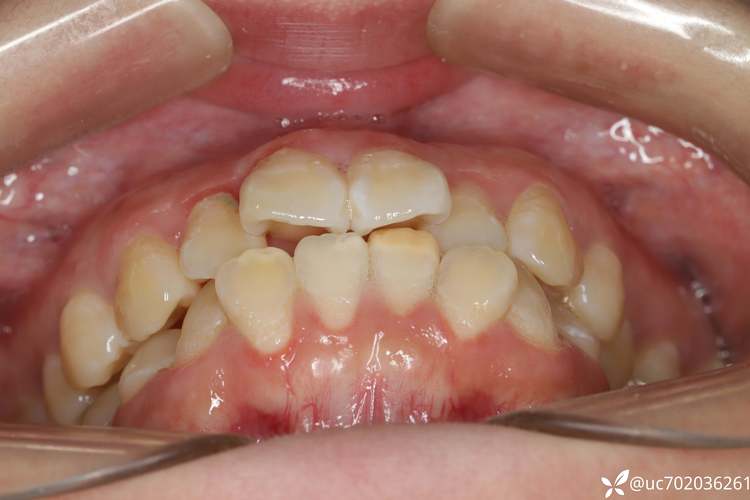

视频开头常呈现医生对患者口腔的全面检查:包括口内照(显示牙齿排列、前突程度)、X光片(头颅侧位片观察颌骨关系、牙根位置)、口内扫描(获取牙齿3D模型,模拟排齐效果),关键画面是医生通过头影测量数据讲解,如“SNA角(上颌骨相对于颅骨的位置)正常,但牙齿前突量达10mm,需拔除4颗第一前磨牙,为前牙内收提供12-14mm空间”,此阶段视频会强调“个性化方案”,避免患者误认为“所有龅牙都要拔牙”。

- 关闭拔牙间隙(6-12个月):随着牙齿排齐,更换较粗的镍钛丝(0.018英寸)或不锈钢方丝,通过“滑动法”或“关闭曲法”内收前牙,视频特写弓丝上的“滑动槽”,医生用结扎丝将牙齿与弓丝固定,随着前牙逐渐向内移动,拔牙间隙逐渐缩小(此阶段是改善龅牙侧貌的关键,视频会对比前牙内收过程中的唇部变化)。

效果展示:直观对比治疗前后面型

视频结尾通常展示患者的治疗前后对比:口内照可见牙齿从拥挤、前突变为整齐、排列整齐;面部照可见嘴唇不再外翻,侧面轮廓更流畅,“鼻-唇-颏”协调性改善;部分视频还会拍摄患者治疗后的采访,如“以前不敢大笑,现在可以自信露齿笑了”。